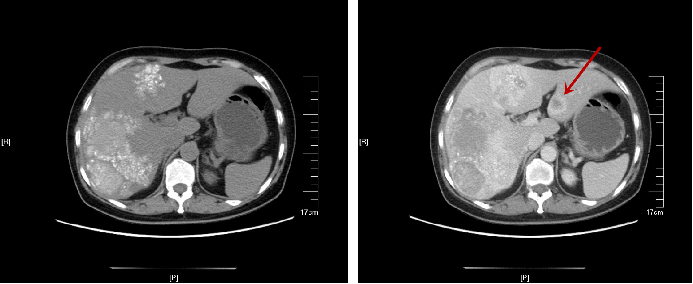

患者左肝为转移病灶,但右肝病灶性质无法明确,进一步行PET-CT检查:

①结肠肝曲肠壁明显增厚,FDG代谢增高,转移可能大;肠周数枚小结节,FDG代谢目前未见明显增高;肝左叶外侧段局灶性FDG代谢增高,MT不除外。

②肝脏明显增大,两叶广泛颗粒样钙化伴局部囊性密度影,考虑肝棘球蚴病可能。

△治疗前